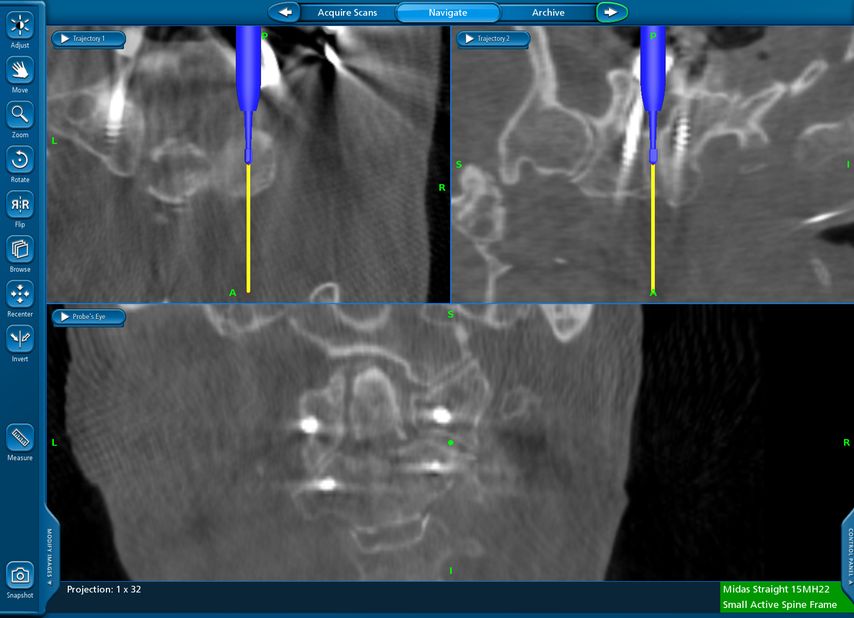

Beispiel für die Implantation zervikaler Pedikelschrauben. In diesem Fall kam es bei einem 61-jährigen Patienten 10 Jahre nach anteriorer zervikaler Diskektomie und Fusion (ACDF) C4/5 und ventraler Verplattung C4–6 zu einer Ankylosierung auch von C6/7. Nach Sturz kam es zu einer Fraktur bei C6/7 mit begleitender Bogenfraktur und auch Beteiligung der dorsalen Ligamenta (Abb. 1 und 2). Klinisch bestanden ausgeprägte Nackenschmerzen und kein neurologisches Defizit. Es wurde die Indikation der dorsalen Verschraubung von C4 auf Th1 gestellt. Intraoperativ wurde routinemäßig zusätzlich eine kleine Referenzschraube in einer Lamina – entfernt von der Dornfortsatz-Referenzklemme für die Navigation – gesetzt. Mit dieser konnte intraoperativ die Genauigkeit der Navigation exakt überprüft werden (Abb. 4 und 5). Mittels navigierter High-Speed-Fräse wurden die Schraubenkanäle vorgebohrt (Abb. 6), im Anschluss wurde der Bohrkanal ausgetastet und die Schrauben wurden implantiert. Abbildung 7 zeigt eine Röntgenkontrolle 3 Monate postoperativ.

Abb. 4: Screenshot der Navigationssoftware intraoperativ (Stealth Station S7). Es erfolgt die intraoperative Verifizierung der Navigationsgenauigkeit mittels kleiner Schraube in der Lamina, positioniert idealerweise entfernt von der Dornfortsatz-Referenzklemme. Die navigierte Fräse wird im Situs exakt auf die Schraubenmitte gerichtet, und die Navigation bestätigt die Genauigkeit | |